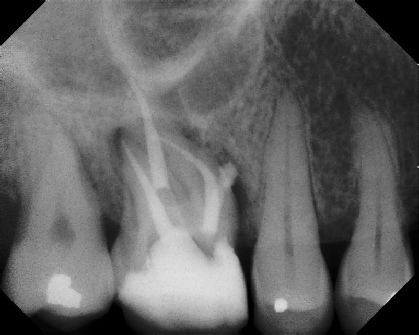

COMPLICATED ANATOMY LARGE LESIONS CALCIFIED CANALS PERFORATION / RESORPTION SEPARATED INSTRUMENTS SURGICAL CASES RETREATMENT / pOST REMOVAL OPEN APICES ACCESS THRU CROWNS Root Canal Case Portfolio

Pre-op Post-op 1 Post-op 2